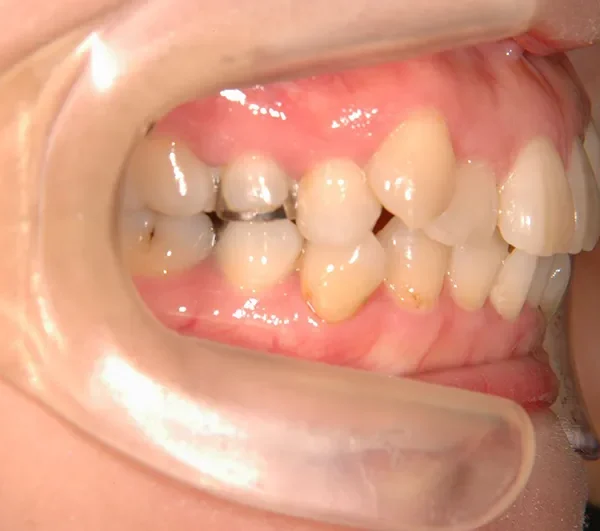

初診時年齢 40歳以上 (女性) 主訴 上下のがたがた・噛み合わない

診断名 叢生 装置名

上下のがたがたと噛み合わない事を主訴に来院されました。

歯は抜かずに矯正治療しました。

治療回数35回、2年8ヶ月の治療期間で矯正治療を終了しました。

噛み合わせが安定する事で、大きくなっていた咬筋が正常な大きさになり、顎のラインもシャープになり大変よろこばれていました。

治療終了後